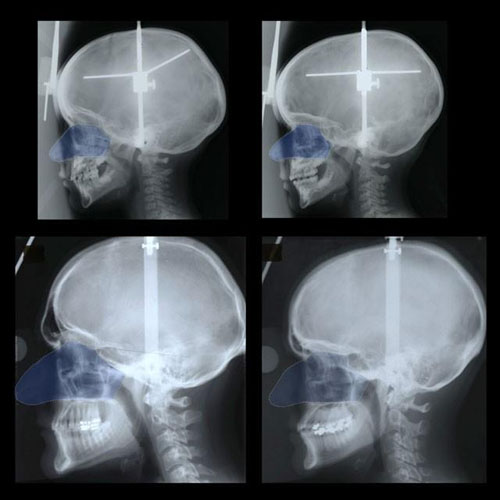

Holton和他的研究团队的实验对象是 38个参与爱荷华州面部增长研究项目( Iowa Facial Growth Study)的欧洲人,研究者从他们 3岁到20 几岁一直定期地测量他们身体的各项指标,他们发现,一般情况下,从出生到青春期,男孩和女孩鼻子的大小无异。而从这之后,差异则逐渐越来越明显了。“即使他们体型是一样大的”, Holton说,“但男性因肌肉组织增长的需要而有更大的鼻子。”